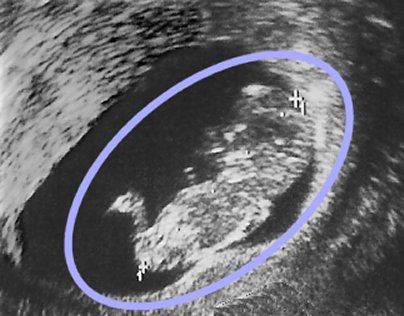

Пример эхограммы

На данной эхограмме, сделанной на третьем месяце беременности, изображен плод мужского пола (голова, тело и ноги ясно видны внутри голубого овала).